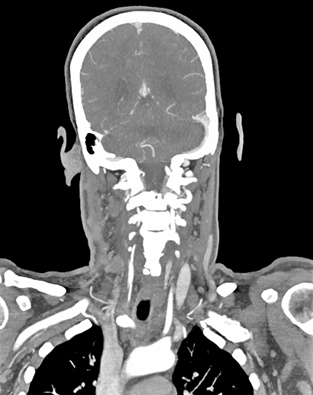

When treating neurovascular disease, time is brain — and precision is everything. Surface both suspected and unexpected findings, optimize workflows and expedite treatment with Aidoc’s Full Brain AI Solution.

Aidoc’s Full Brain Solution runs all relevant AI algorithms on a facility’s CT scans to flag both expected and unexpected findings — regardless of the scan’s primary purpose.

Enhance triage with image-based AI that runs on all CTA scans regardless of protocol.